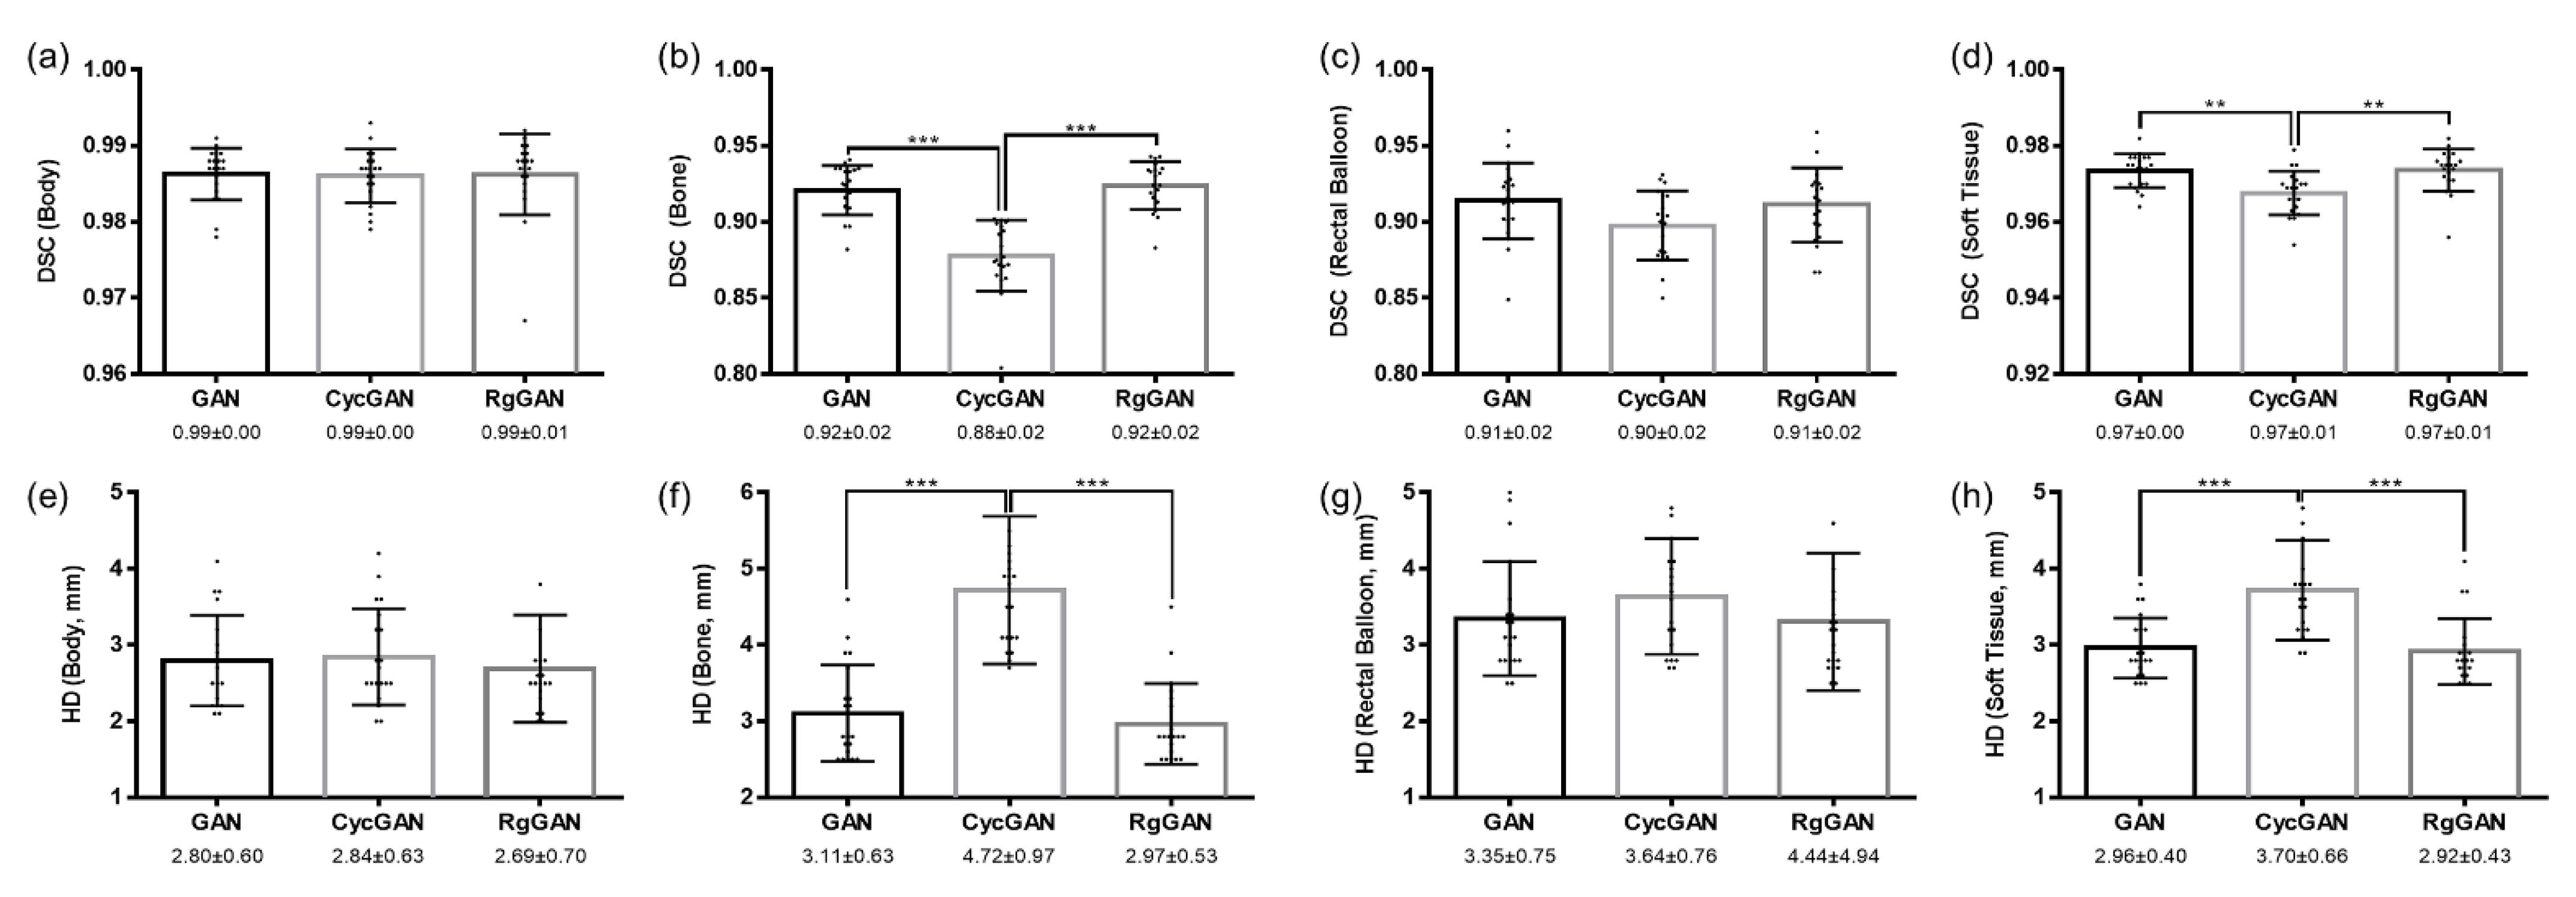

3.2. Image Quality

3.3. Dosimetric Comparison